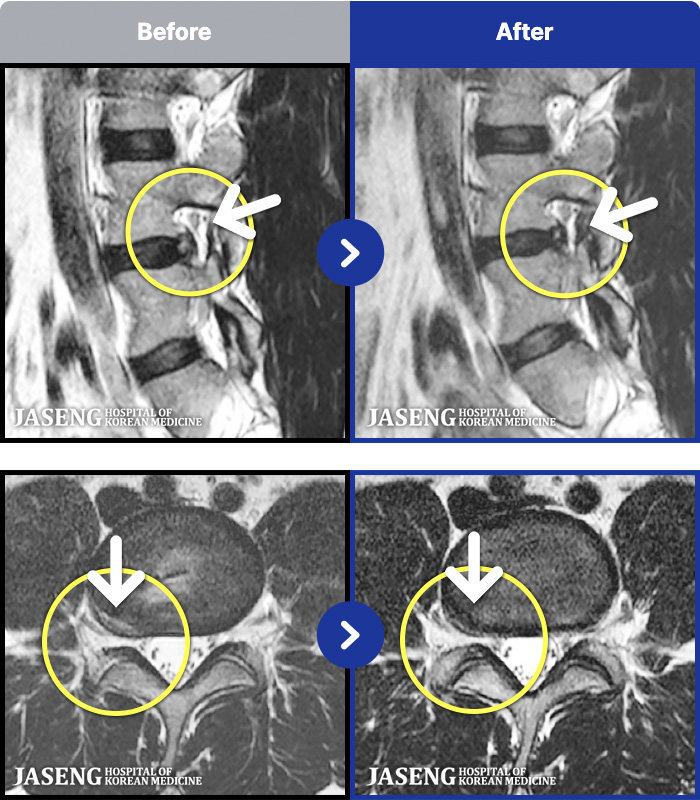

MRI ġ

MRI ũ ʸ Ȯϼ.